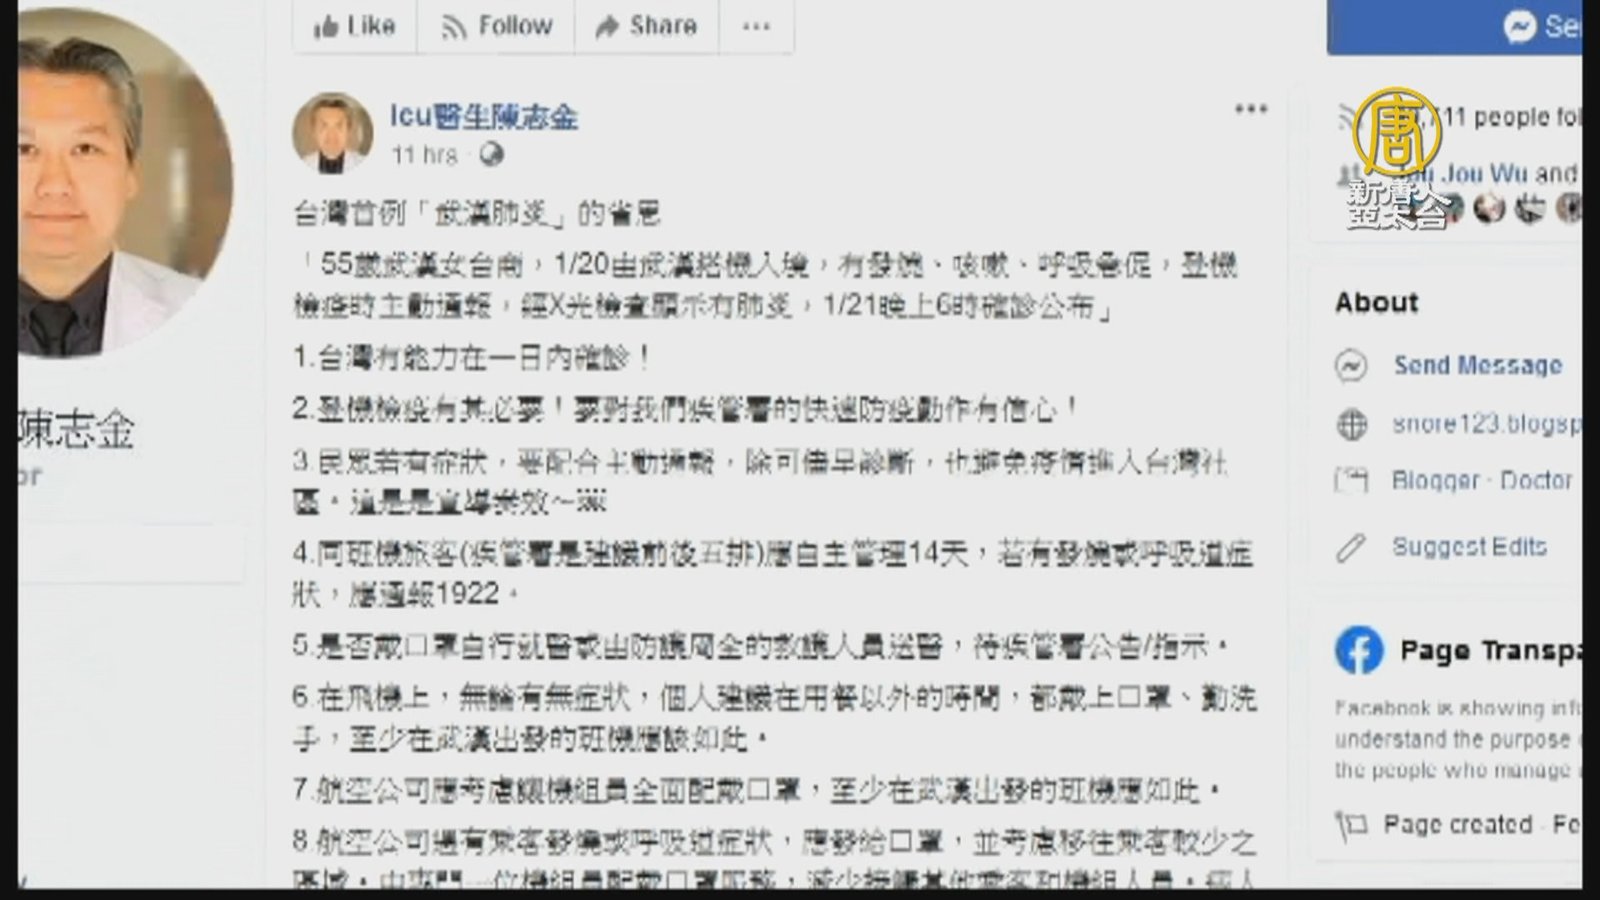

武漢肺炎女台商退燒 重症醫師寫下「10點省思」

2020-02-14 13:45:23針對台灣首位確診罹患「武漢肺炎」的50多歲女台商,防疫醫師黃婉婷表示,這名女台商從1月11日就開始出現發燒、咳嗽、喉嚨痛的症狀,但因為對大陸當地的醫療沒信心才沒有到醫院就診,一直到1月20日從武漢搭機回台才看醫生。女台商說,在飛機上全程配戴口罩,只有在吃飯時摘下。同機46人也被防疫指揮中心列入觀察。醫師黃婉婷表示,女台商的X光顯示兩側肺炎,目前狀況穩定,已無發燒等症狀,只需給予低濃度氧氣,無需插管。另外,重症醫師陳志金在臉書分享 台灣出現首例武漢肺炎的10點省思,指出台灣有能力在一日內確診病患,未來民眾有